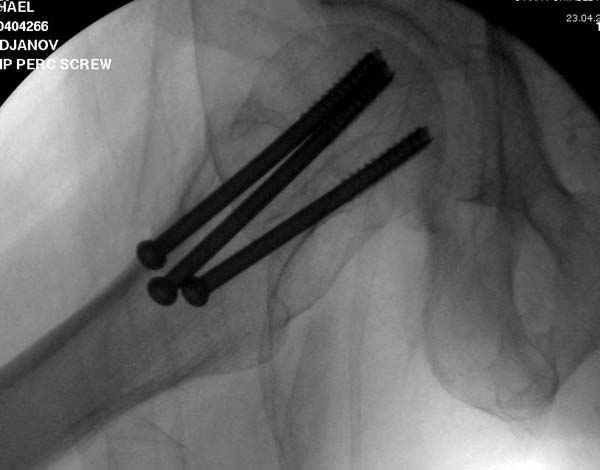

Профилактику дальнейшего раскола неполного перелома шейки провели тремя канюлированными шурупами.

в течение первых 72 часов после перелома, остеосинтез тремя спонгиозными шурупами.

Наверное речь идет насчет parallel guide из набора. Применяем по возможности всегда, но,

как видно на снимке, не всегда получается

паралельно.

Такие несмещенные переломы обычно для молодых резидентов, и бывают технические неточности, но в этом случае посчитали фиксацию адекватной.